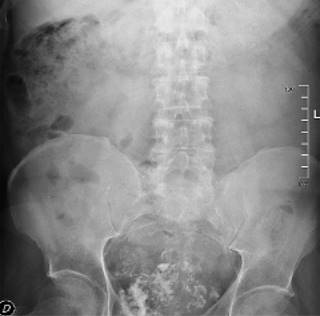

Varón de 62 años, fumador de 20 paquetes-año, con antecedentes personales de artritis reumatoide en tratamiento con certolizumab que es valorado en atención primaria por presentar episodios esporádicos de hematuria macroscópica relacionados con el ejercicio, de cuatro meses de evolución. A la exploración física presenta molestias a la palpación en fosa ilíaca derecha sin masas asociadas. Tras realización de análisis de sangre incluyendo antígeno prostático específico (PSA) y ecografía de aparato urinario y vejiga, que informa de «próstata heterogénea y mal definida, con calcificaciones y aumentada de volumen en unos 60 cm3», es remitido a urología. Se realiza una cistoscopía en la que se aprecia «litiasis de 1.5-2 cm y una neoformación papilar de aspecto superficial < 1 cm en proximidad del meato ureteral derecho», por lo que se decide llevar a cabo una cistolitotricia endoscópica y resección transuretral vesical (RTU). La liberación de la «litiasis vesical» se describe como «aspecto de tumor calcificado» y se aprecia un «tumor vesical extenso sólido de pared anterior y fondo calcificado en superficie». Ante estos hallazgos, se solicita una radiografía (Rx) de abdomen (Figura 1) y se envían muestras a anatomía patológica (AP). Posteriormente se realiza tomografía axial computarizada (TAC) abdominopélvica con contraste (Figura 2)-, que informa de «masa infiltrante exofítica que afecta a la vertiente anteroinferior de la vejiga con signos sugestivos de probable infiltración de la rama iliopubiana derecha y del músculo obturador homolateral, contactando asimismo con la vertiente anterior de la próstata, sin plano de separación grasa. Neoplasia vesical infiltrante (T4) con adenopatía sospechosa en cadena ilíaca externa derecha, sin lesiones de tracto urinario superior ni a distancia».

La radiología simple (radiografía y ecografía) son los pilares del algoritmo diagnóstico, siendo sus características radiológicas la matriz cartilaginosa, las calcificaciones en «palomita de maíz» y los bordes mal definidos (Figura 1).